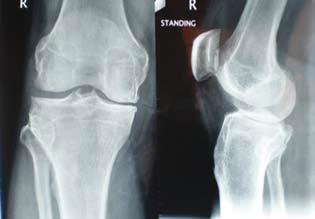

X光片可見膝關節之間的空間收窄,顯示出現退化。

■人體有143 個關節,當中大關節包括膝關節、髖關節,它們都是受力較多的關節,容易因勞損出現退化。